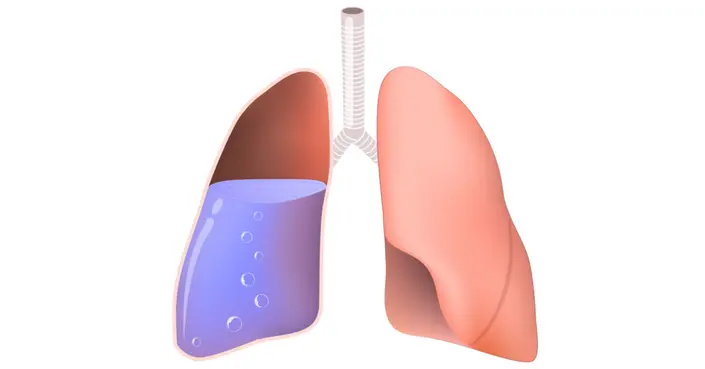

نعم، يمكن أن يسبب ماء الرئة الوفاة في بعض الحالات، خاصة إذا لم يُعالج بشكل فوري وفعال. الأمر لا يتعلق بتجمع الماء بحد ذاته فقط، بل بالسبب الأساسي وراء هذا التجمع ومدى تأثيره على وظائف الرئة الحيوية. توجد حالتان رئيسيتان تتراكم فيهما السوائل في الرئة وهما:

- الانصباب الجنبي (Pleural Effusion): وهو تراكم السوائل في الحيز الجنبي المحيط بالرئتين.

يحدث الانصباب الجنبي عندما تتجمع السوائل في الحيز الجنبي، وهو الفراغ الرقيق الموجود بين الغشاء المحيط بالرئتين والغشاء المبطن لجدار الصدر. عندما يتراكم الكثير من السائل، يضغط على الرئة ويمنعها من التوسع بشكل كامل، مما يجعل التنفس صعباً.

أنواع السوائل المتراكمة وتأثيرها

تختلف خطورة الحالة أيضاً بناءً على نوع السائل المتراكم في الحيز الجنبي:

- الرشحة (Transudate): سائل مائي نقي عادة ما ينتج عن خلل في توازن الضغوط في الأوعية الدموية، ويعتبر أقل خطورة.

- النضحة (Exudate): سائل غني بالبروتين والخلايا، غالباً ما ينتج عن التهاب أو إصابة، ويعد أكثر خطورة ويشير إلى مشكلة طبية كامنة جدية.